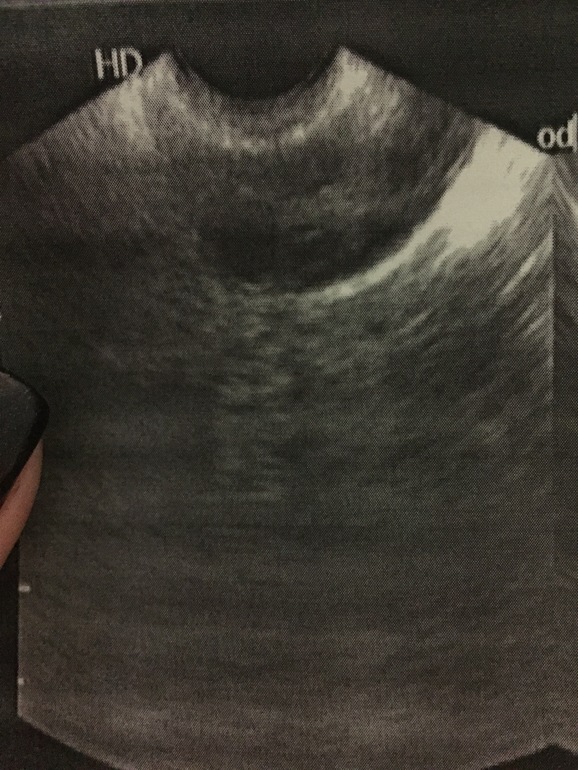

Девчоночки.кто разбирается.Сходила на фолликулометрию на 8дц.В правом яичнике имеются единичные фолликулы до 8,9 мм и жидкостный элемент с ненапряженной стенкой 15*7 мм.Я спросила это дом.фолликул,а она говорит скорее всего это желтое тело еще не ушло с прошлого цикла..стенка если ненапряженная,это по моему не может быть дф да?у меня был в прошлый цикл жт на этом месте(19*14)...может кто-то может отличить .пью шалфей со 2дц.может действительно это дф.фото с этим элементом

Стенка не напряженная да?дф по-моему должен быть более круглый и с четкой стенкой